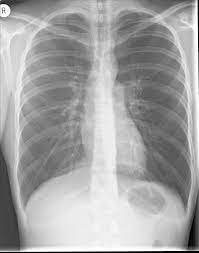

🩻 Right Lower Lobe Pneumonia

PA chest X-ray showing consolidation in the right lower lobe with air bronchograms.

1 PA chest X-ray showing consolidation in the right lower lobe with air bronchograms.